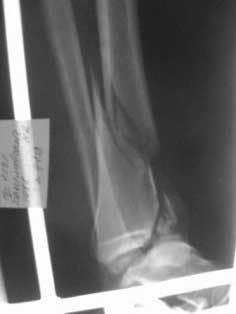

Уважаемые коллеги, хотелось бы услышать как прооперировать этот злополучный перелом

(интерисует погружной синтез)?

Извините за качество снимков! Если сможите разобрать, то: 1)Какой доступ

предпочтительней? 2)Каким образом устранить тенденцию к подвывиху кпереди (не будет ли

проблемой оскольчатость переднего края)? Заранее спасибо! С уважением А.Мелёшкин!